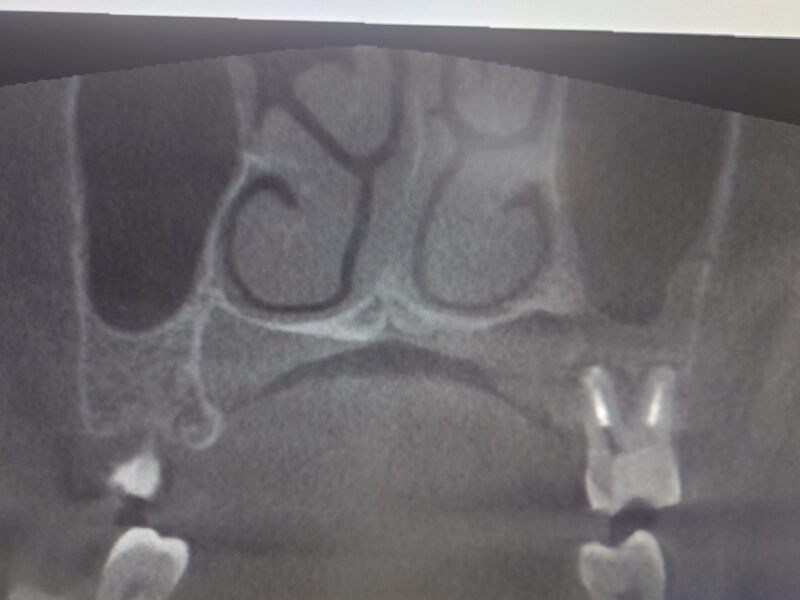

歯が場合の場合 CTを撮影するとわかります 。上の写真のように 写真右上が白く曇って見えます

通常 片方だけが曇っている場合は歯性上顎洞炎を疑います。治療法として抜歯が選択されることもあります。